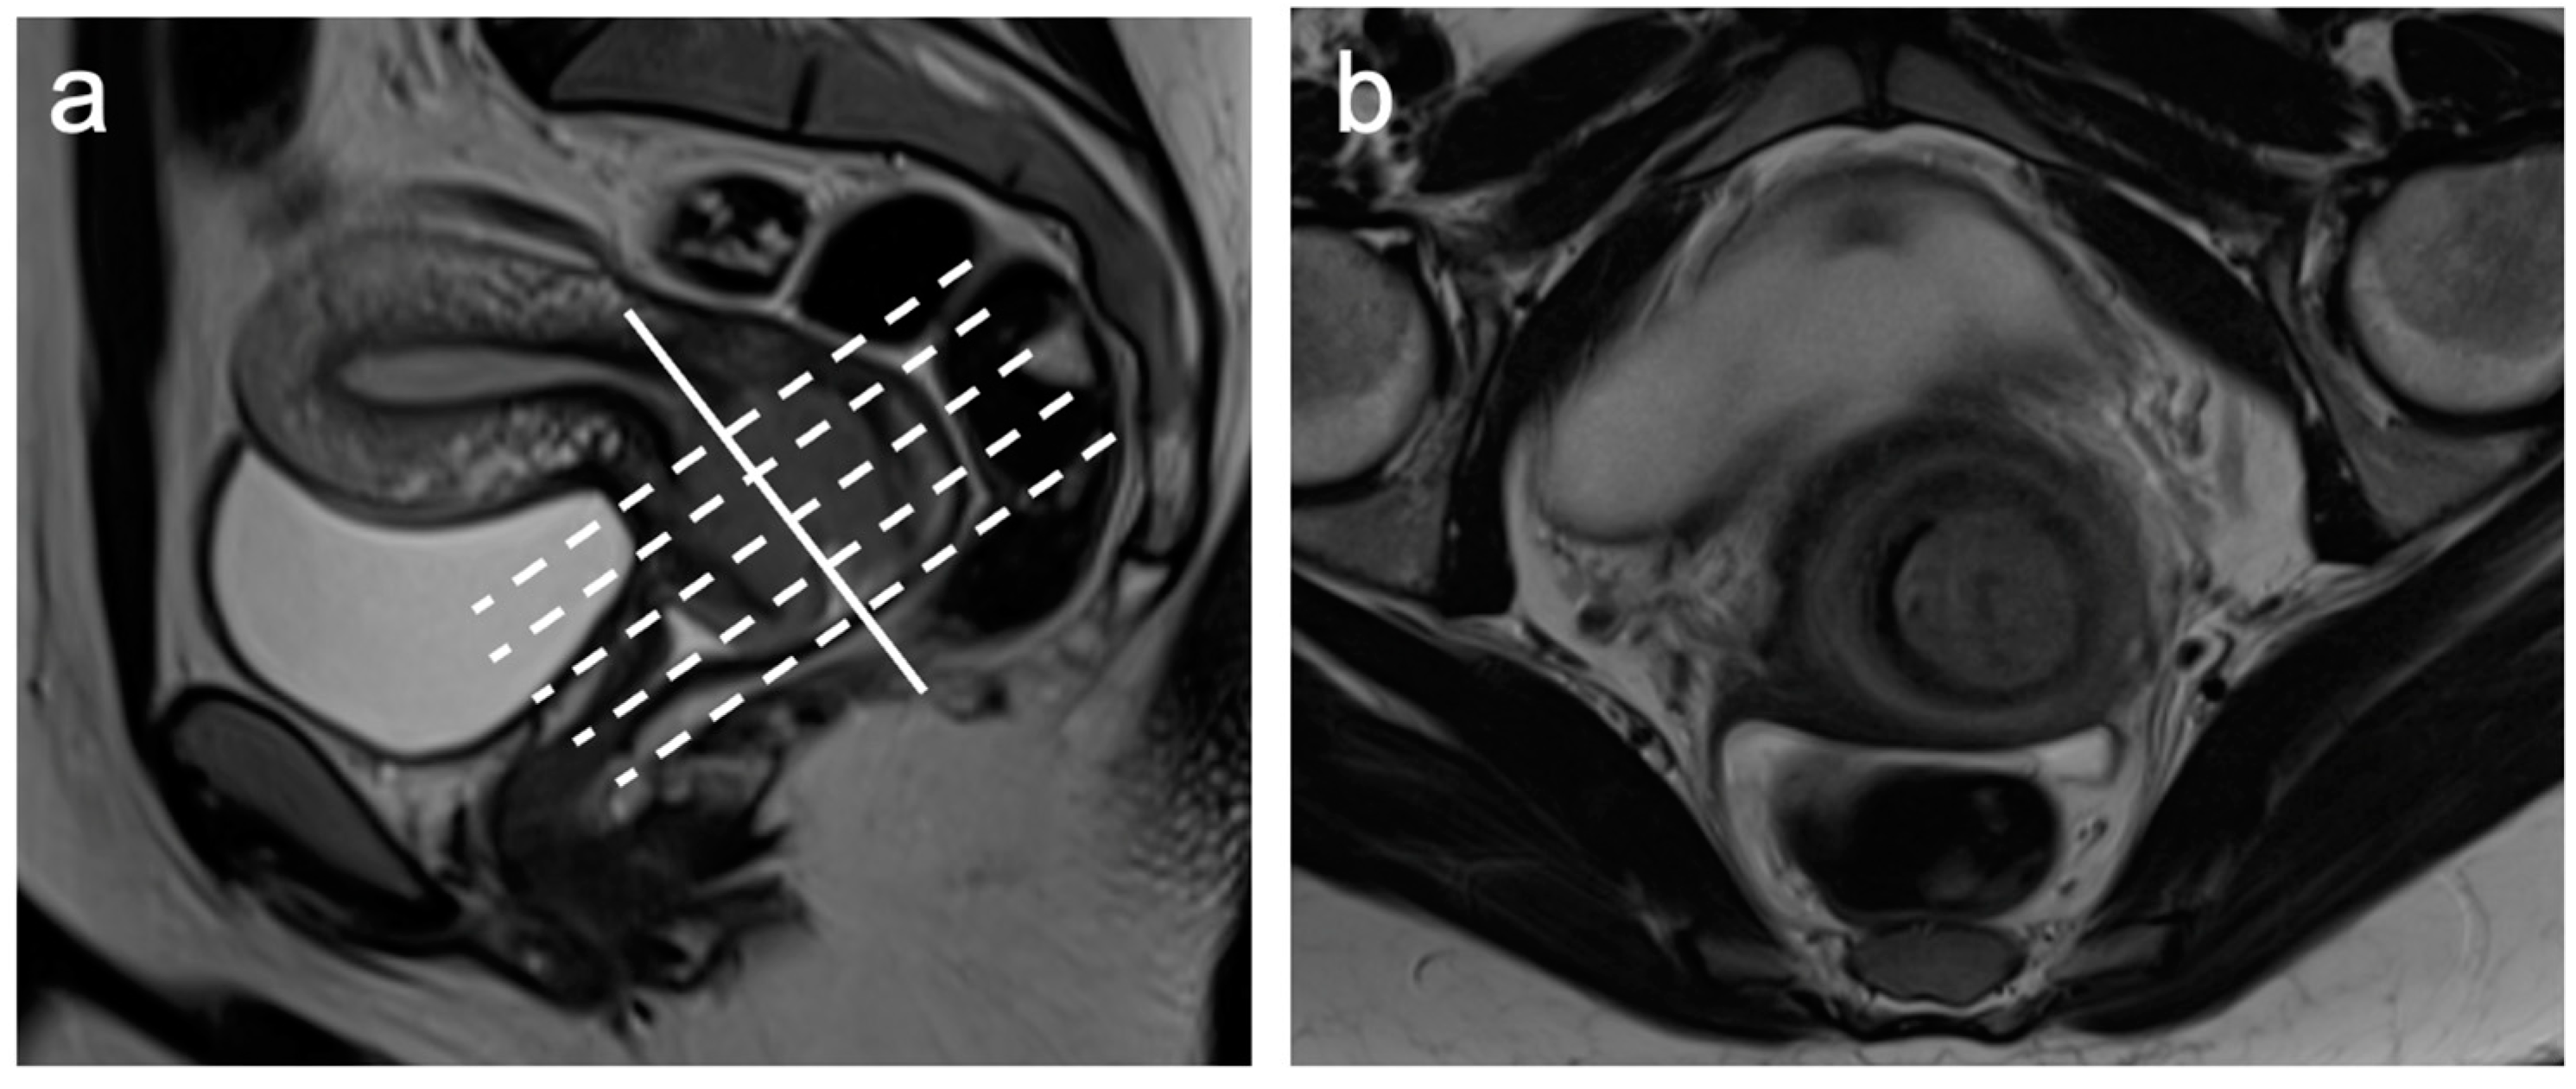

| Small FOV Sagittal T2WI | Accurate tumour size, local staging (e.g., vaginal, bladder, rectal invasion) |

| Small FOV Axial oblique T2WI | Local staging, parametrial and pelvic sidewall involvement |

| Sagittal and axial oblique DWI and ADC maps (corresponding to sagittal and axial oblique T2WI) | Identifying small isointense tumours, unsuspected bone metastases |